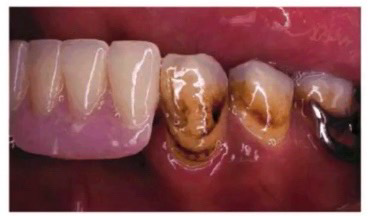

Betel nuts stain